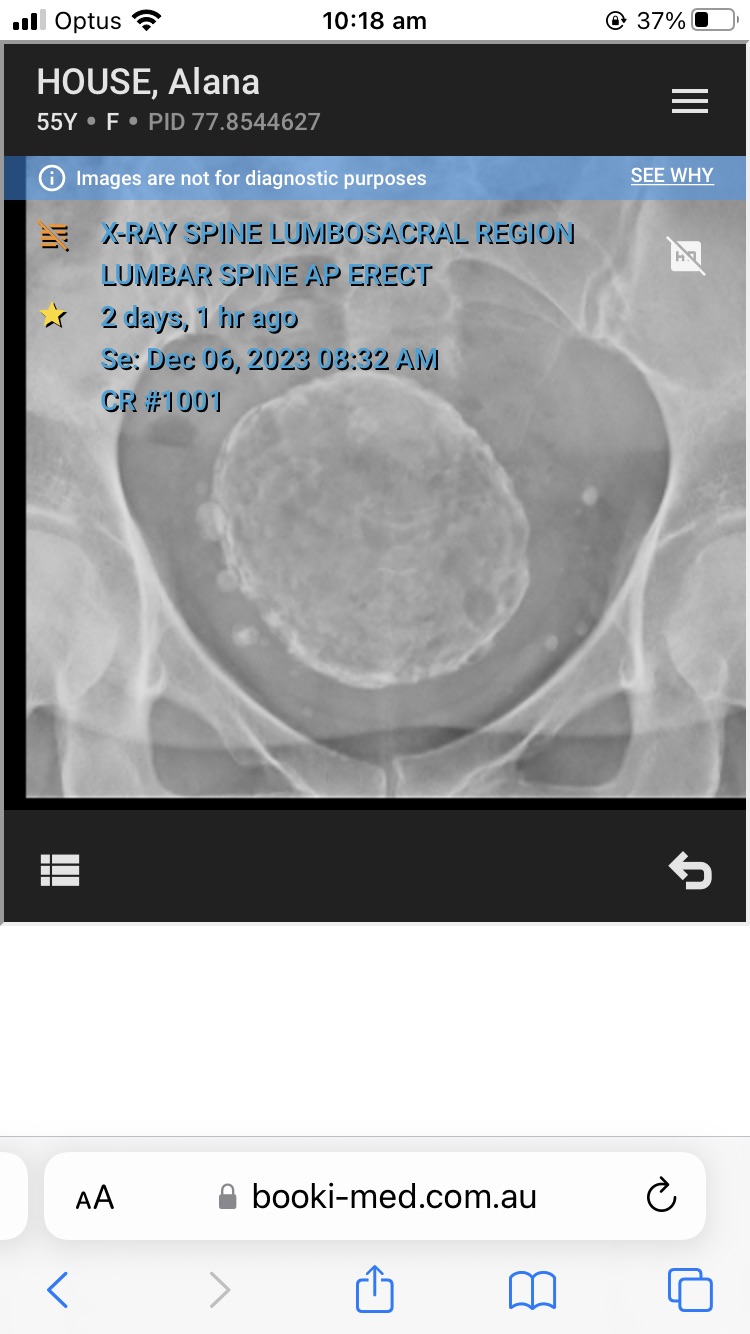

In other news, remember how panicked I was by my ultrasound last week? Well I was sent the x-ray of my pelvis, which threw me into a tailspin.

This is what it looked like:

I had a brain snap about what the huge mass was and started hyperventilating and frantically Googling “abnormal pelvic x-ray”.

Anyways after about 10 minutes of cold-sweat dread and Googling I suddenly realised it was Freddie the Fibroid.

Long-term blog followers may recall that Freddie was discovered in my uterus about eight or nine years ago. He was calculated to be around the size of a three-month old fetus.

It might be just the angle, but Freddie looks absolutely freaking enormous.

Freddie’s size may explain why I am having back and hip pain. Dr Google tells me that when fibroids get that big they can press on your sciatic nerve.

I don’t have the results of the ultrasound yet, but when I do I will head to the doctor for advice on next steps. I am thinking I might finally have to resign myself to major surgery.